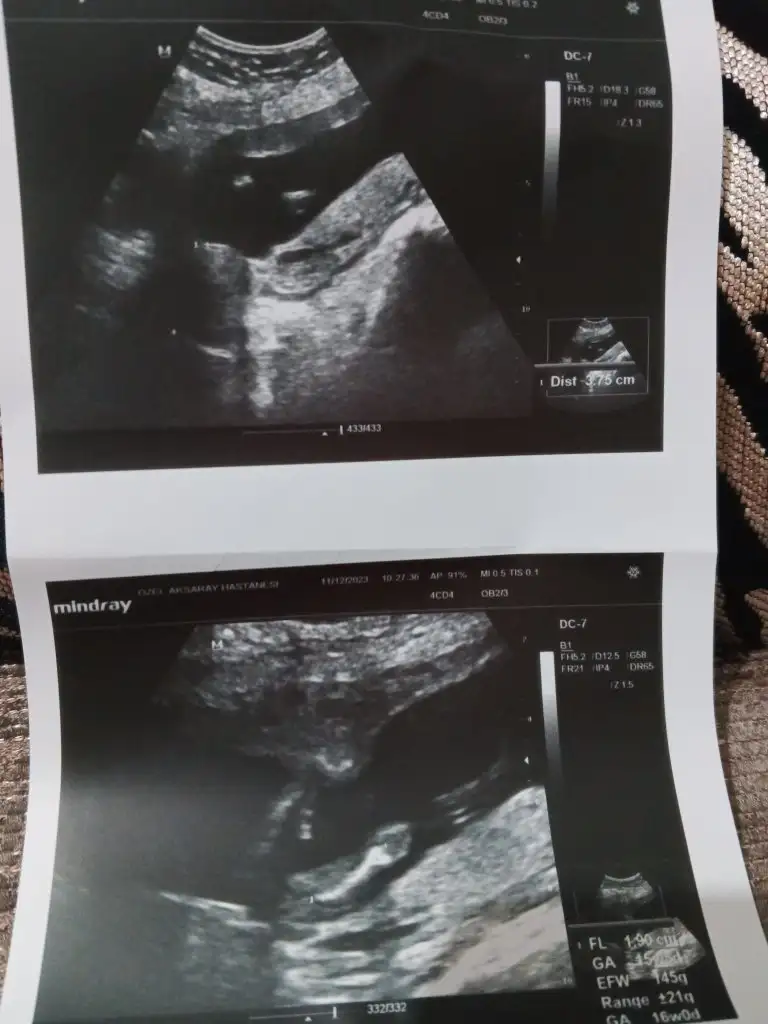

Kizlar bende 16 hafta 6 günlük hamileyim doktor dün kız dedi 100/de 95 dedi. İperleyen haflalarda cinsiyet değişikliği olqn varmı sizce benimkiside degisirmi benim durumumda olan varmı. Allah rızası için banada cevap yazarmisiniz benim GB opan varmı

Sevde49 gönderdim bu resim geçen ayın... Dünkü doktor kontrolü ntrolunde çekilen resimleride attım bakarmisiniz sayfamda Allah rızası için